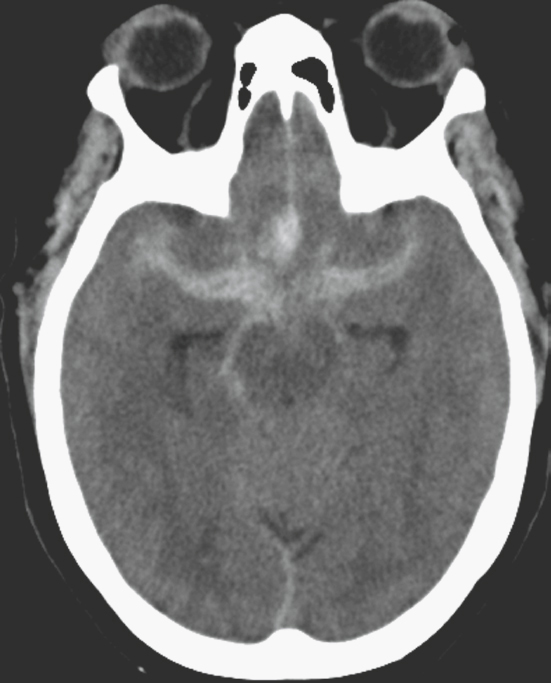

On axial images, transtentorial herniation can be assessed by evaluating the circummesencephalic cisterns. With downward transtentorial herniation, the ambient cisterns and suprasellar cistern will become effaced (Fig. 30.3). When there is upward transtentorial herniation, the quadrigeminal plate cistern becomes effaced (Fig. 30.4).

FIGURE 30.3 Axial CT image in a patient with supratentorial mass effect resulting in downward transtentorial herniation. There is effacement of the suprasellar and ambient cisterns (white arrow) with preservation of the quadrigeminal plate cistern (black arrow).